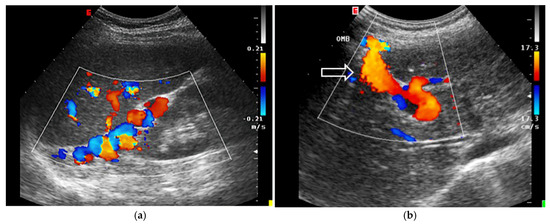

Assessing Venous Congestion in Acute and Chronic Heart Failure: A Review of Splanchnic, Cardiac and Pulmonary Ultrasound: Part 1: Conventional B-Mode, Colordoppler, and Vexus Protocol

Background/Objectives: Heart failure (HF) causes systemic and regional haemodynamic alterations that extend beyond the heart, profoundly affecting splanchnic circulation. Venous congestion is a hallmark of heart failure (HF) and a major determinant of clinical deterioration and multiorgan dysfunction. The splanchnic venous system—comprising the portal, hepatic, and renal veins—acts as a key reservoir for intravascular volume redistribution. Conventional ultrasound (US), using grayscale and Doppler imaging, offers a direct, non-invasive approach to visualize these haemodynamic changes. This review, Part 1 of a two-part series, summarizes the current evidence and clinical applications of conventional US for assessing splanchnic, cardiac and pulmonary vascular alterations in patients with HF. Methods: A systematic review was performed in PubMed, Embase, and the Cochrane Library up to current date, following PRISMA 2020 guidelines. Eligible studies included adult human investigations evaluating splanchnic vascular changes in HF using B-mode, color Doppler, or pulsed Doppler ultrasonography. Exclusion criteria were pediatric, animal, or non-English studies and non-standard imaging methods. Data on ultrasonographic parameters, haemodynamic correlations, and prognostic value were extracted and qualitatively synthesized; Results: A total of 148 eligible studies (n ≈ 7000 patients) demonstrated consistent associations between HF severity and alterations in splanchnic, cardiac and pulmonary flow. Findings included increased bowel wall thickness, portal vein dilation with elevated pulsatility, and monophasic or reversed hepatic vein waveforms, all correlating with higher right atrial pressure and adverse clinical outcomes. The integration of these parameters into the Venous Excess Ultrasound (VExUS) framework enhanced detection of systemic venous congestion, in addition to the study of the cardiac and pulmonary circulation. Conclusions: Conventional ultrasound assessment of splanchnic vasculature provides valuable, reproducible insight into systemic congestion in HF. Incorporating hepatic and portal Doppler indices into standard evaluation protocols may improve risk stratification, optimize decongestion therapy, and guide management. Further prospective randomized and outcome-driven studies are required before VExUS-based therapeutic thresholds can be universally recommended and define prognostic thresholds. Full article